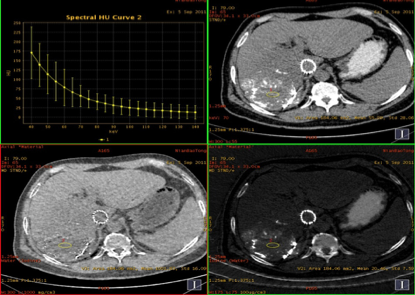

男性,56岁,肝癌栓塞术后复查。

能谱分析

平扫:碘9.03,水1018.90

动脉期:碘8.56,水1016.22

静脉期:碘8.25,水1016.37

缩小ROI后放在病灶碘油未沉积区比较如下:

平扫:碘2.05,水1001.88

动脉期:碘1.66,水1009.80

结论:此例平扫、增强多期碘基物质定量无显著差异。栓塞治疗效果较好。

临床优势:肝癌栓塞后,因碘油和术后炎性反应的影响,短期内难以评估手术效果。通过能谱成像GSI分析,比较增强后碘含量与平扫时碘含量(有时可用水含量)的变化及变化趋势,来判断肝癌病灶是否还有强化,评估栓塞治疗的疗效和预后,并可指导临床进一步治疗。